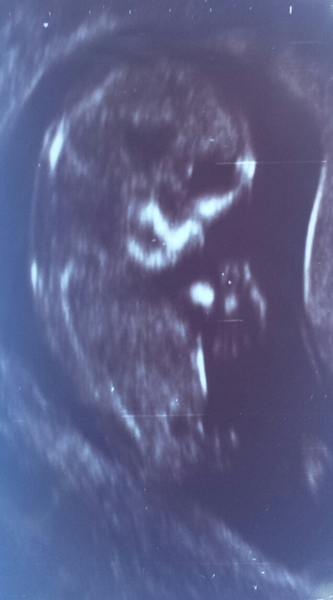

Congrats on your scan jmac. That's a great pic!

I had my scan this morning which was fine. Baby growing well, I think a couple of days ahead of last count, but they won't change EDD now. Moving well. The cyst has also grown which is less happy, though at this stage it is just something they watch. If it's still there at the next scan I'll get referred to a consultant which is a pain because (a) Soton hospital is ~1hr drive with traffic, and (b) I hope it won't interfere with my desire to have baby in a midwife led unit.

And so exciting for those of you knowing gender. I was looking at the scan thinking, you know if you're a boy or a girl but we don't know. I can't wait to find out!!